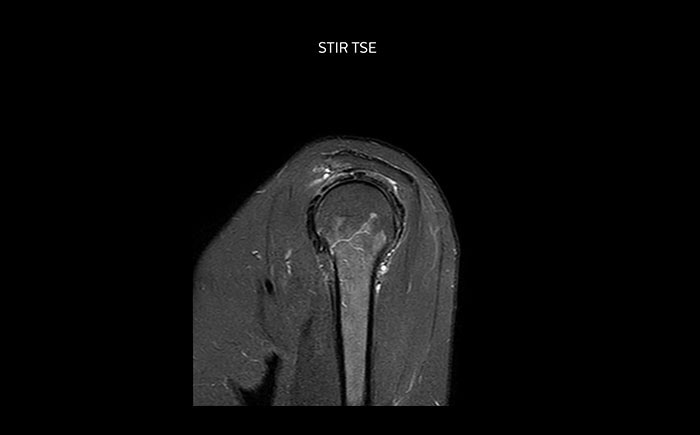

Bildgebung der Nierenarterien ohne Kontrastmittel mit Prodiva 1.5T.